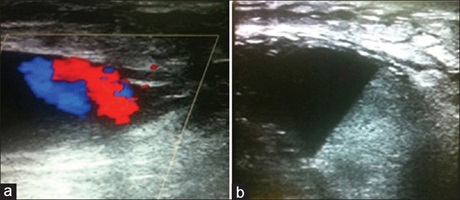

Ultrasound-guided Thrombin Injection for the Treatment of Iatrogenic Pseudoaneurysm of the Right Brachial Artery

Sadisu Mohammed Maaji, Madhan Kumar, Sanjeev Kumar, Dr. Gurpreet Singh Gulati (Author)

71-75